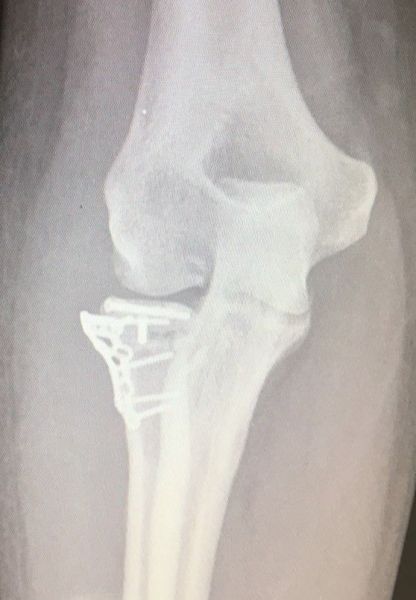

4. Displaced fracture of distal end of the right radius (wrist fracture) in a 63-year-old female.

Treatment. Open reduction internal fixation

I. Before operation, anteroposterior x-ray of the wrist II. Before operation, lateral x-ray of the wrist IIA. Day of procedure, lateral view IIB. Day of procedure, anteroposterior view